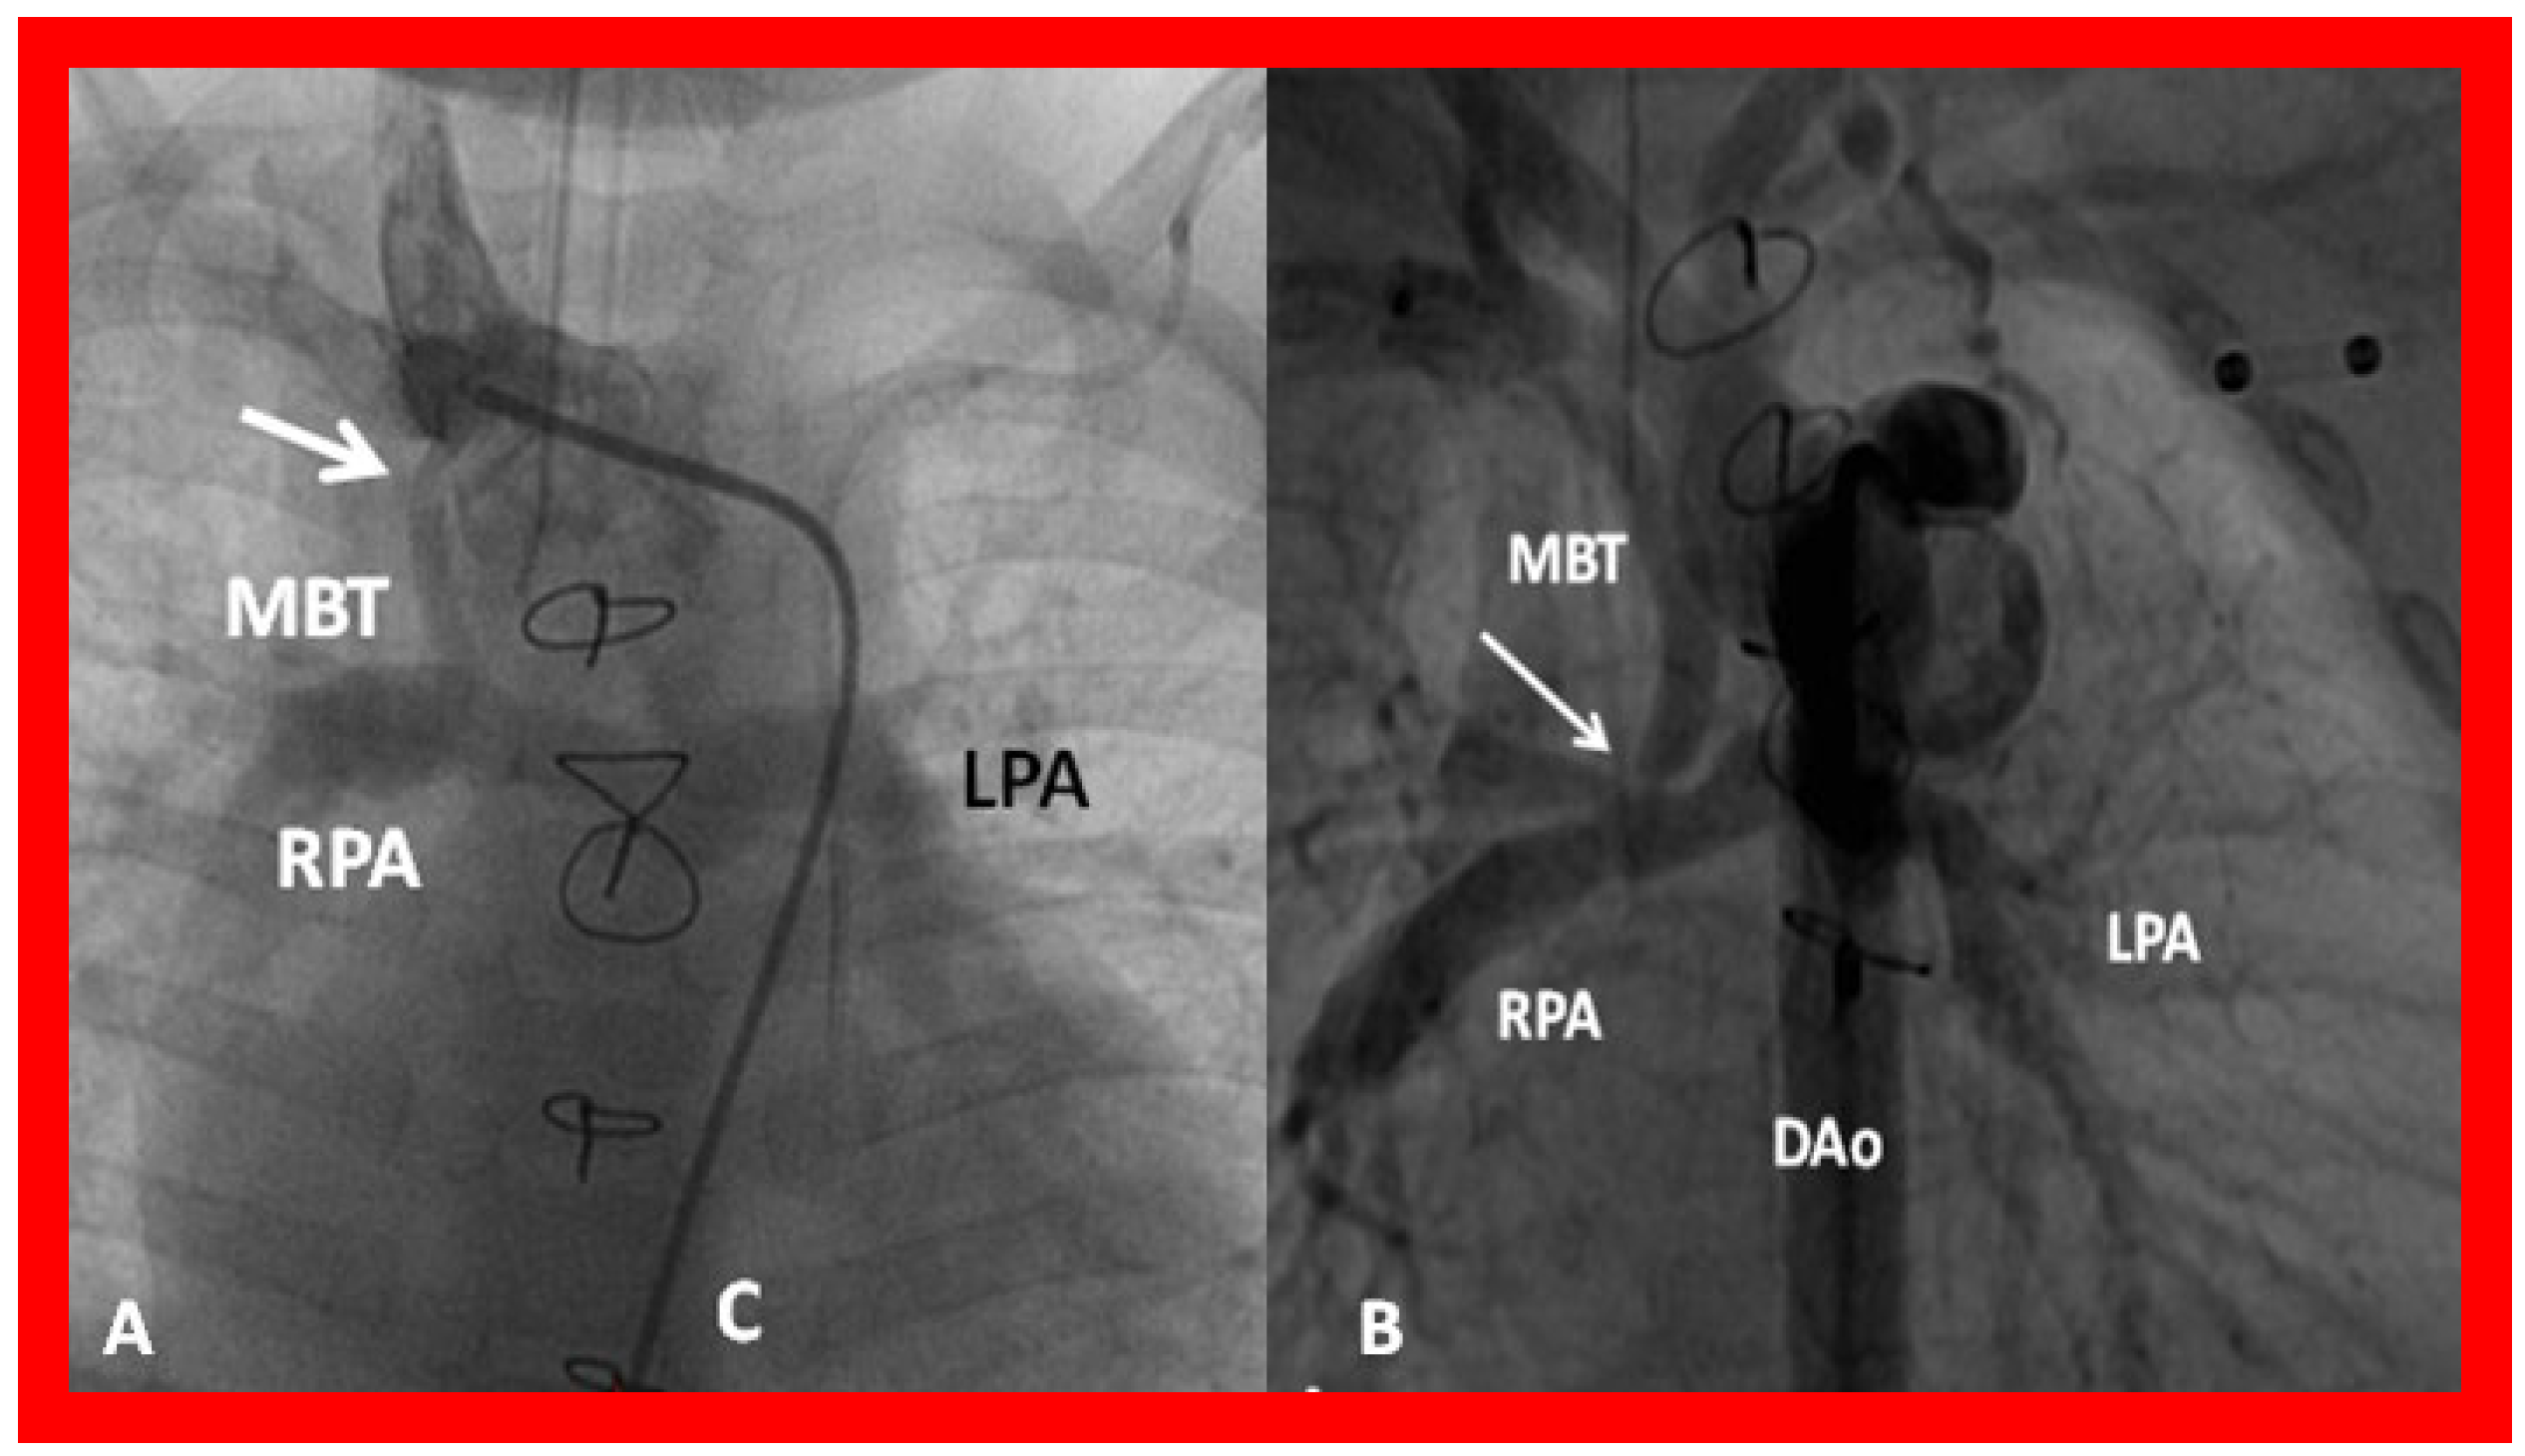

Figure 37. (A) Selected cine frame in a postero–anterior view demonstrating narrowing (arrow) of a modified Blalock–Taussig (MBT) shunt at its junction with the right innominate artery. (B) Similar angiographic frame from a different patient showing narrowing of the MBT (arrow) at its entry into the right pulmonary artery (RPA). C, catheter; DAo, descending aorta; LPA, left pulmonary artery.

Blockage of the aorto–pulmonary shunts may develop during follow up, which may either be complete or partial. Patients with complete blockage, usually due to thrombus formation, typically present with severe cyanosis and respiratory distress. Inability to demonstrate the shunt by color Doppler interrogation in a patient in whom a shunt was demonstrated in prior studies suggests complete shunt blockage. In patients who develop partial blockage, the obstruction may be either at the proximal anastomosis with the subclavian (or innominate) artery or aortic arch, at the distal anastomosis at the entry into the PA, or, rarely, somewhere in between (due to kinking). While these obstructive lesions are easily demonstrable on angiography (Figure 37), these narrowings are somewhat difficult to image by 2D. However, color flow disturbance along with high Doppler flow velocities at the site of obstruction suggest obstruction. Thrombolytic recanalization, transcatheter stent implantation, the surgical revision of the shunt, or bidirectional Glenn may be performed, depending upon the clinical scenario and institutional preference [38].